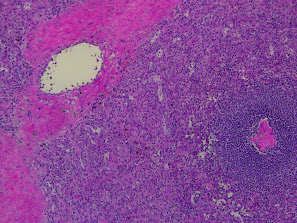

Glande surrénale

Les glandes surrénales sont divisées en leur cortex, c'est à dire la fraction la plus à l'extérieur, et la médulla, qui se situe au centre. Le tout est protégé par une capsule de collagène.

Le cortex transforme le cholestérol en hormones stéroïdiennes. L'arrangement des cellules varie de l'extérieur vers l'intérieur de cette couche et chacune correspond à une spécialisation:

- Zone glomérulée (cellules en amas): minéralocorticoïdes (aldostérone)

- Zone fasciculée (cellules en cordons): glucocorticoïdes (cortisone)

- Zone réticulée (cellules isolées): androgènes, progestérone

La médulla, quant à elle, sécrète les catécholamines: l'adrénaline et hormones apparentées. Ses cellules sont vacuolées et semblent moins denses. La médulla est le tissu qui se décompose le plus vite du corps humain. Même sur une biopsie fixée rapidement, une perte de qualité peut apparaître.